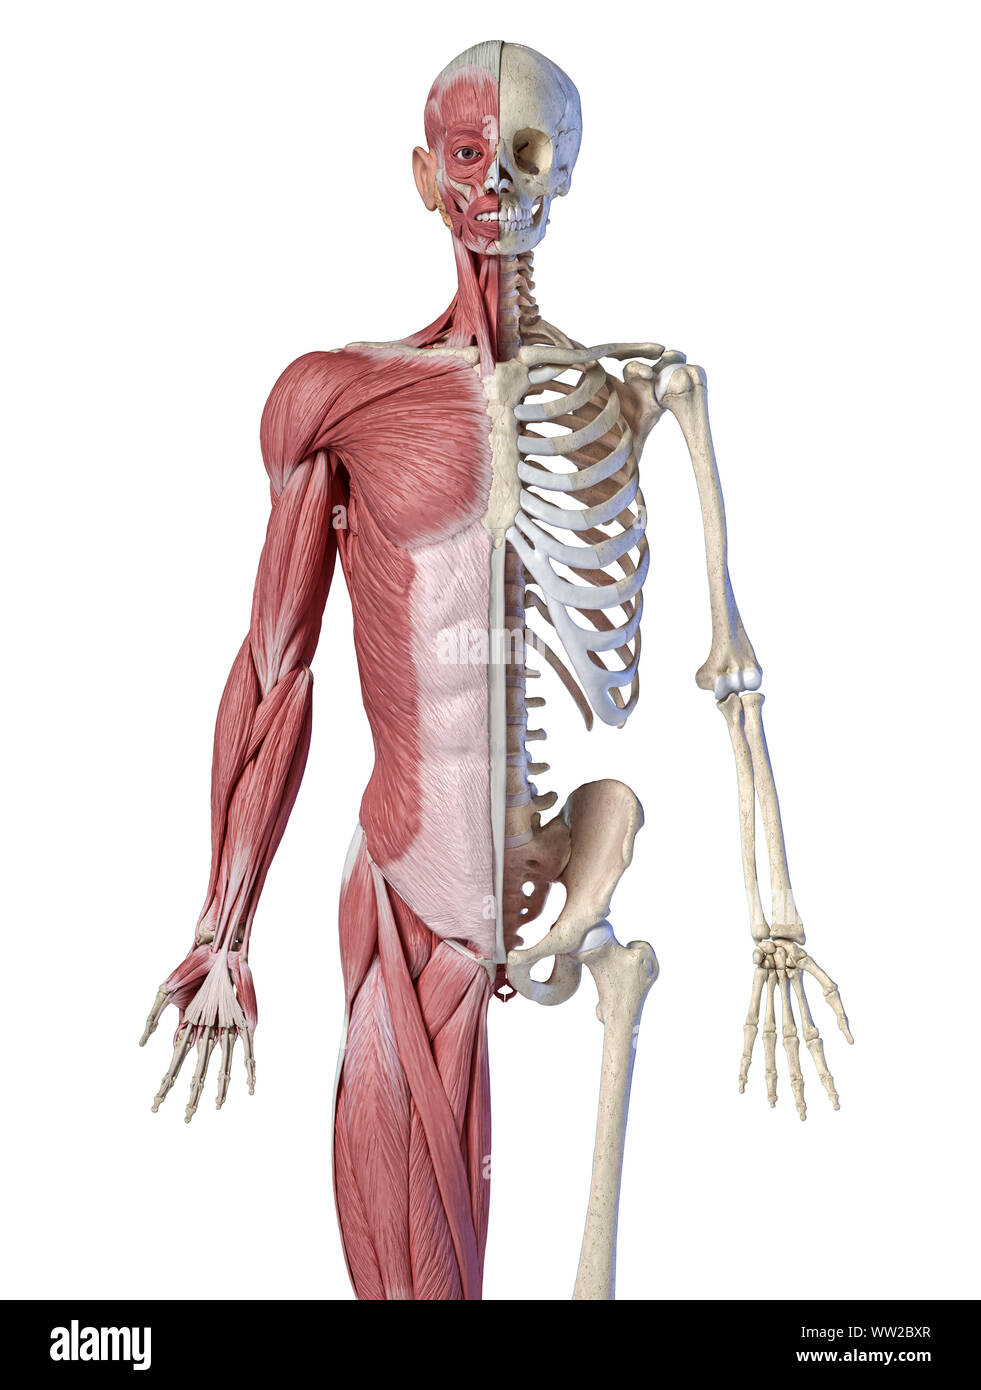

RFWW2BXR–Die männliche Anatomie, 3/4 Abbildung Muskel- und Skeletterkrankungen Systeme, Vorderansicht auf weißem Hintergrund. 3D-Anatomie Illustration.